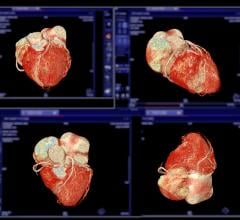

Currently, subtracting bone from neurological CT angiography procedures requires that physicians scan the brain twice, once with contrast and once without contrast, and then manually subtract bone structures from the image to better visualize the vessels and tissue. Toshiba’s SURESubtraction technology automates the bone subtraction process, reducing exam time by a reported 90 percent, according to the manufacturer.

SURESubtraction is an option for Toshiba’s 8-, 16-, 32- and 64-slice CT systems. Given the software’s ability to detect and subtract bone from images, it offers a number of clinical applications, including: